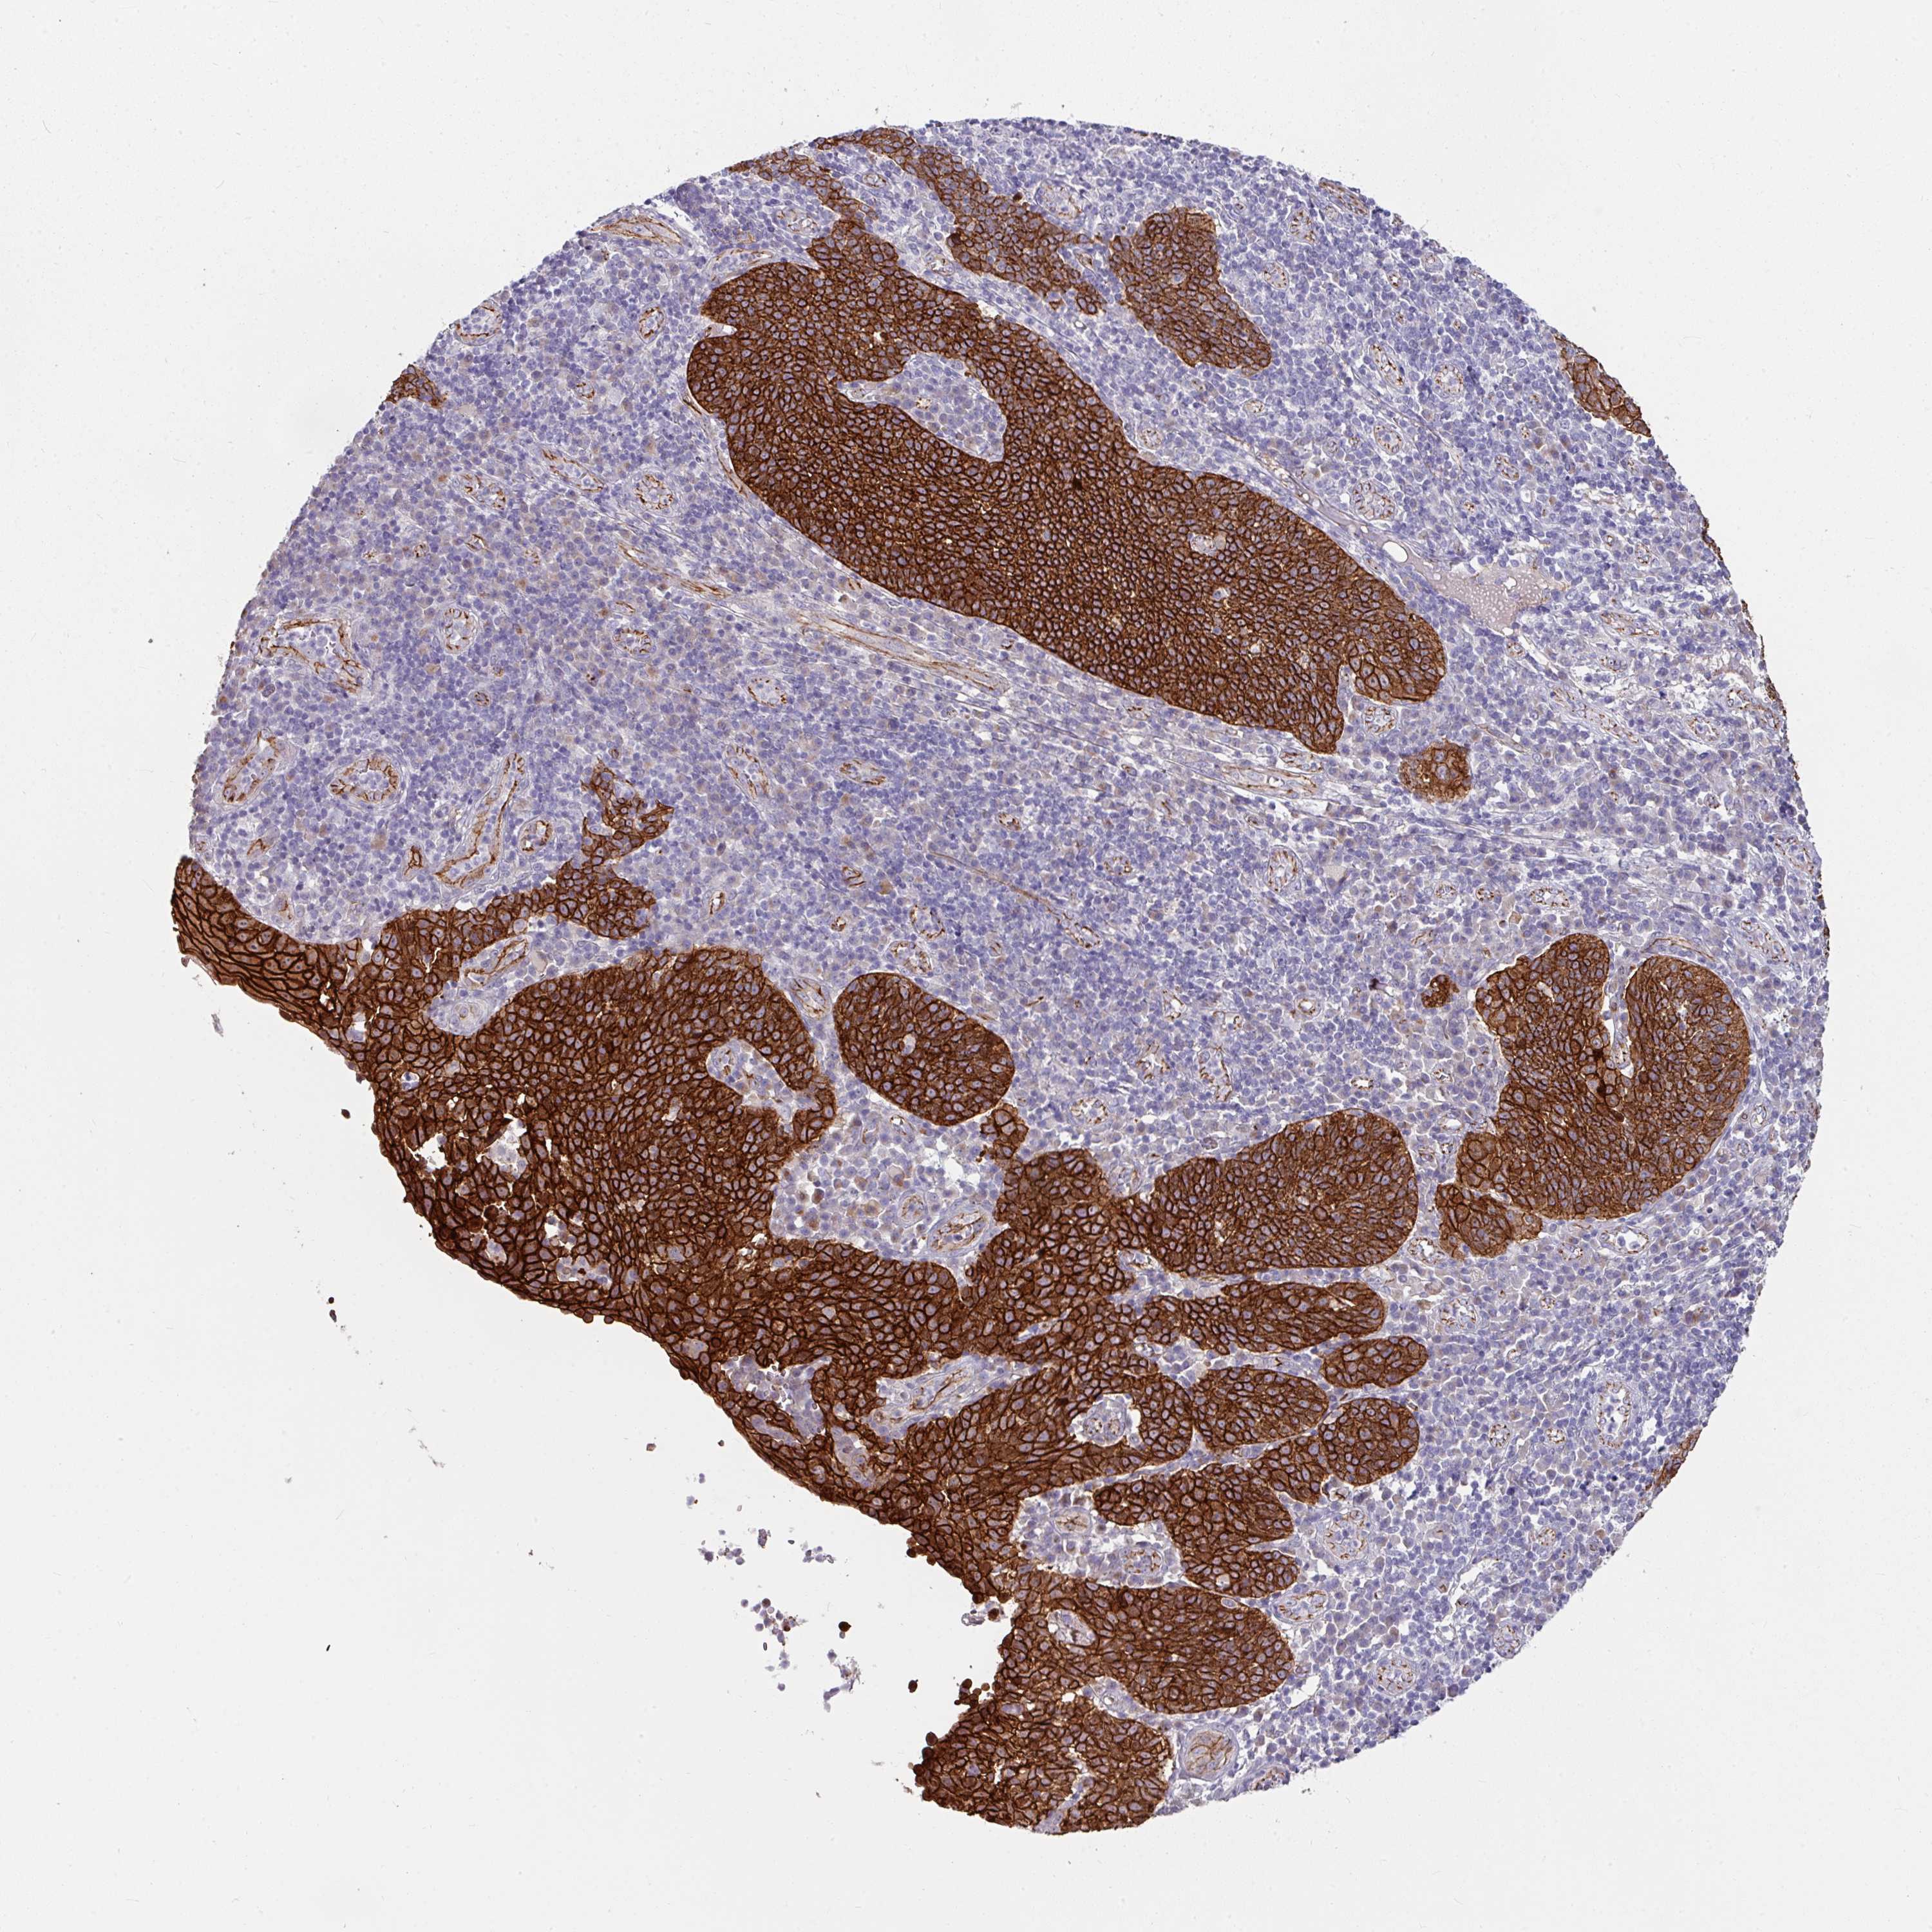

CERVICAL CANCER - Protein expressioni

A mouse-over function shows sample information and annotation data. Click on an image to view it in a full screen mode. Samples can be filtered based on level of antibody staining by selecting one or several of the following categories: high, medium, low and not detected. The assay and annotation is described here.

Note that samples used for immunohistochemistry by the Human Protein Atlas do not correspond to samples in the TCGA dataset.

Antibody stainingi

Antibody staining in the annotated cell types in the current human tissue is reported as not detected, low, medium, or high, based on conventional immunohistochemistry profiling in selected tissues. This score is based on the combination of the staining intensity and fraction of stained cells.

Each image is clickable and will lead to virtual microscopy that enables deeper exploration of all samples and also displays staining intensity scores, fraction scores and subcellular localization as well as patient and tissue information for each sample.

Antibody CAB002139

Squamous cell carcinoma, NOS